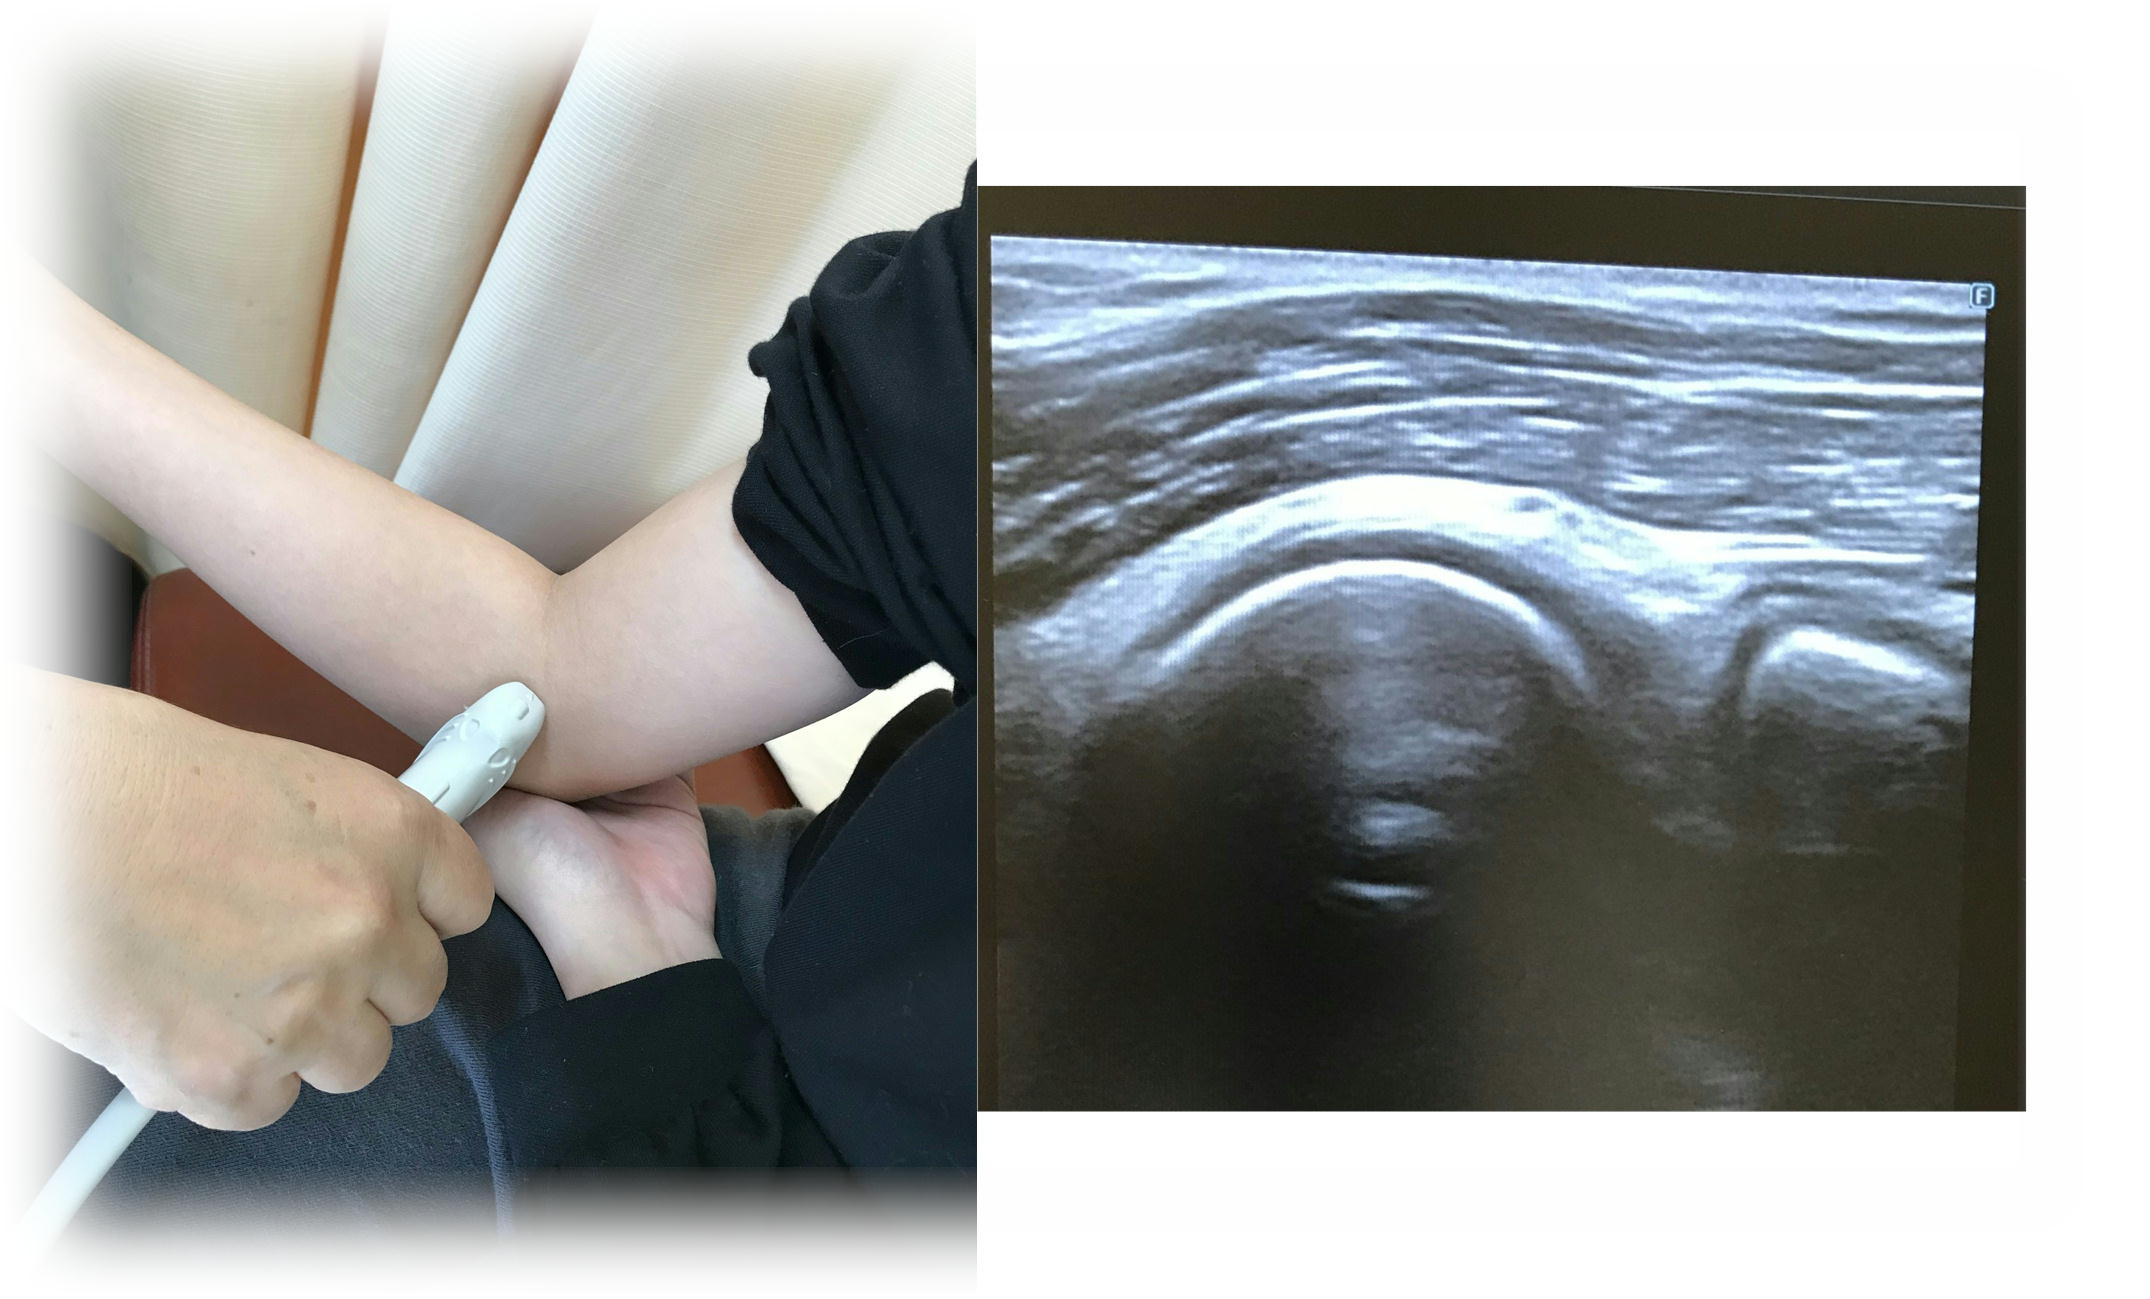

肩の腱板損傷・膝の変形予防

- 施術内容

- 肩の腱板損傷の有無・膝の変形の具合など、エコーで確認しながら、今後の予防のために必要な事を、1人1人に合わせたメニューと施術でアドバイスを行っていきます。

- 「運動」と言われても何をしたら良いかわからない方。「やみくもにしてみたら余計痛くなった」方。「この運動はどうか知りたい」方などにオススメです。

- ¥2000